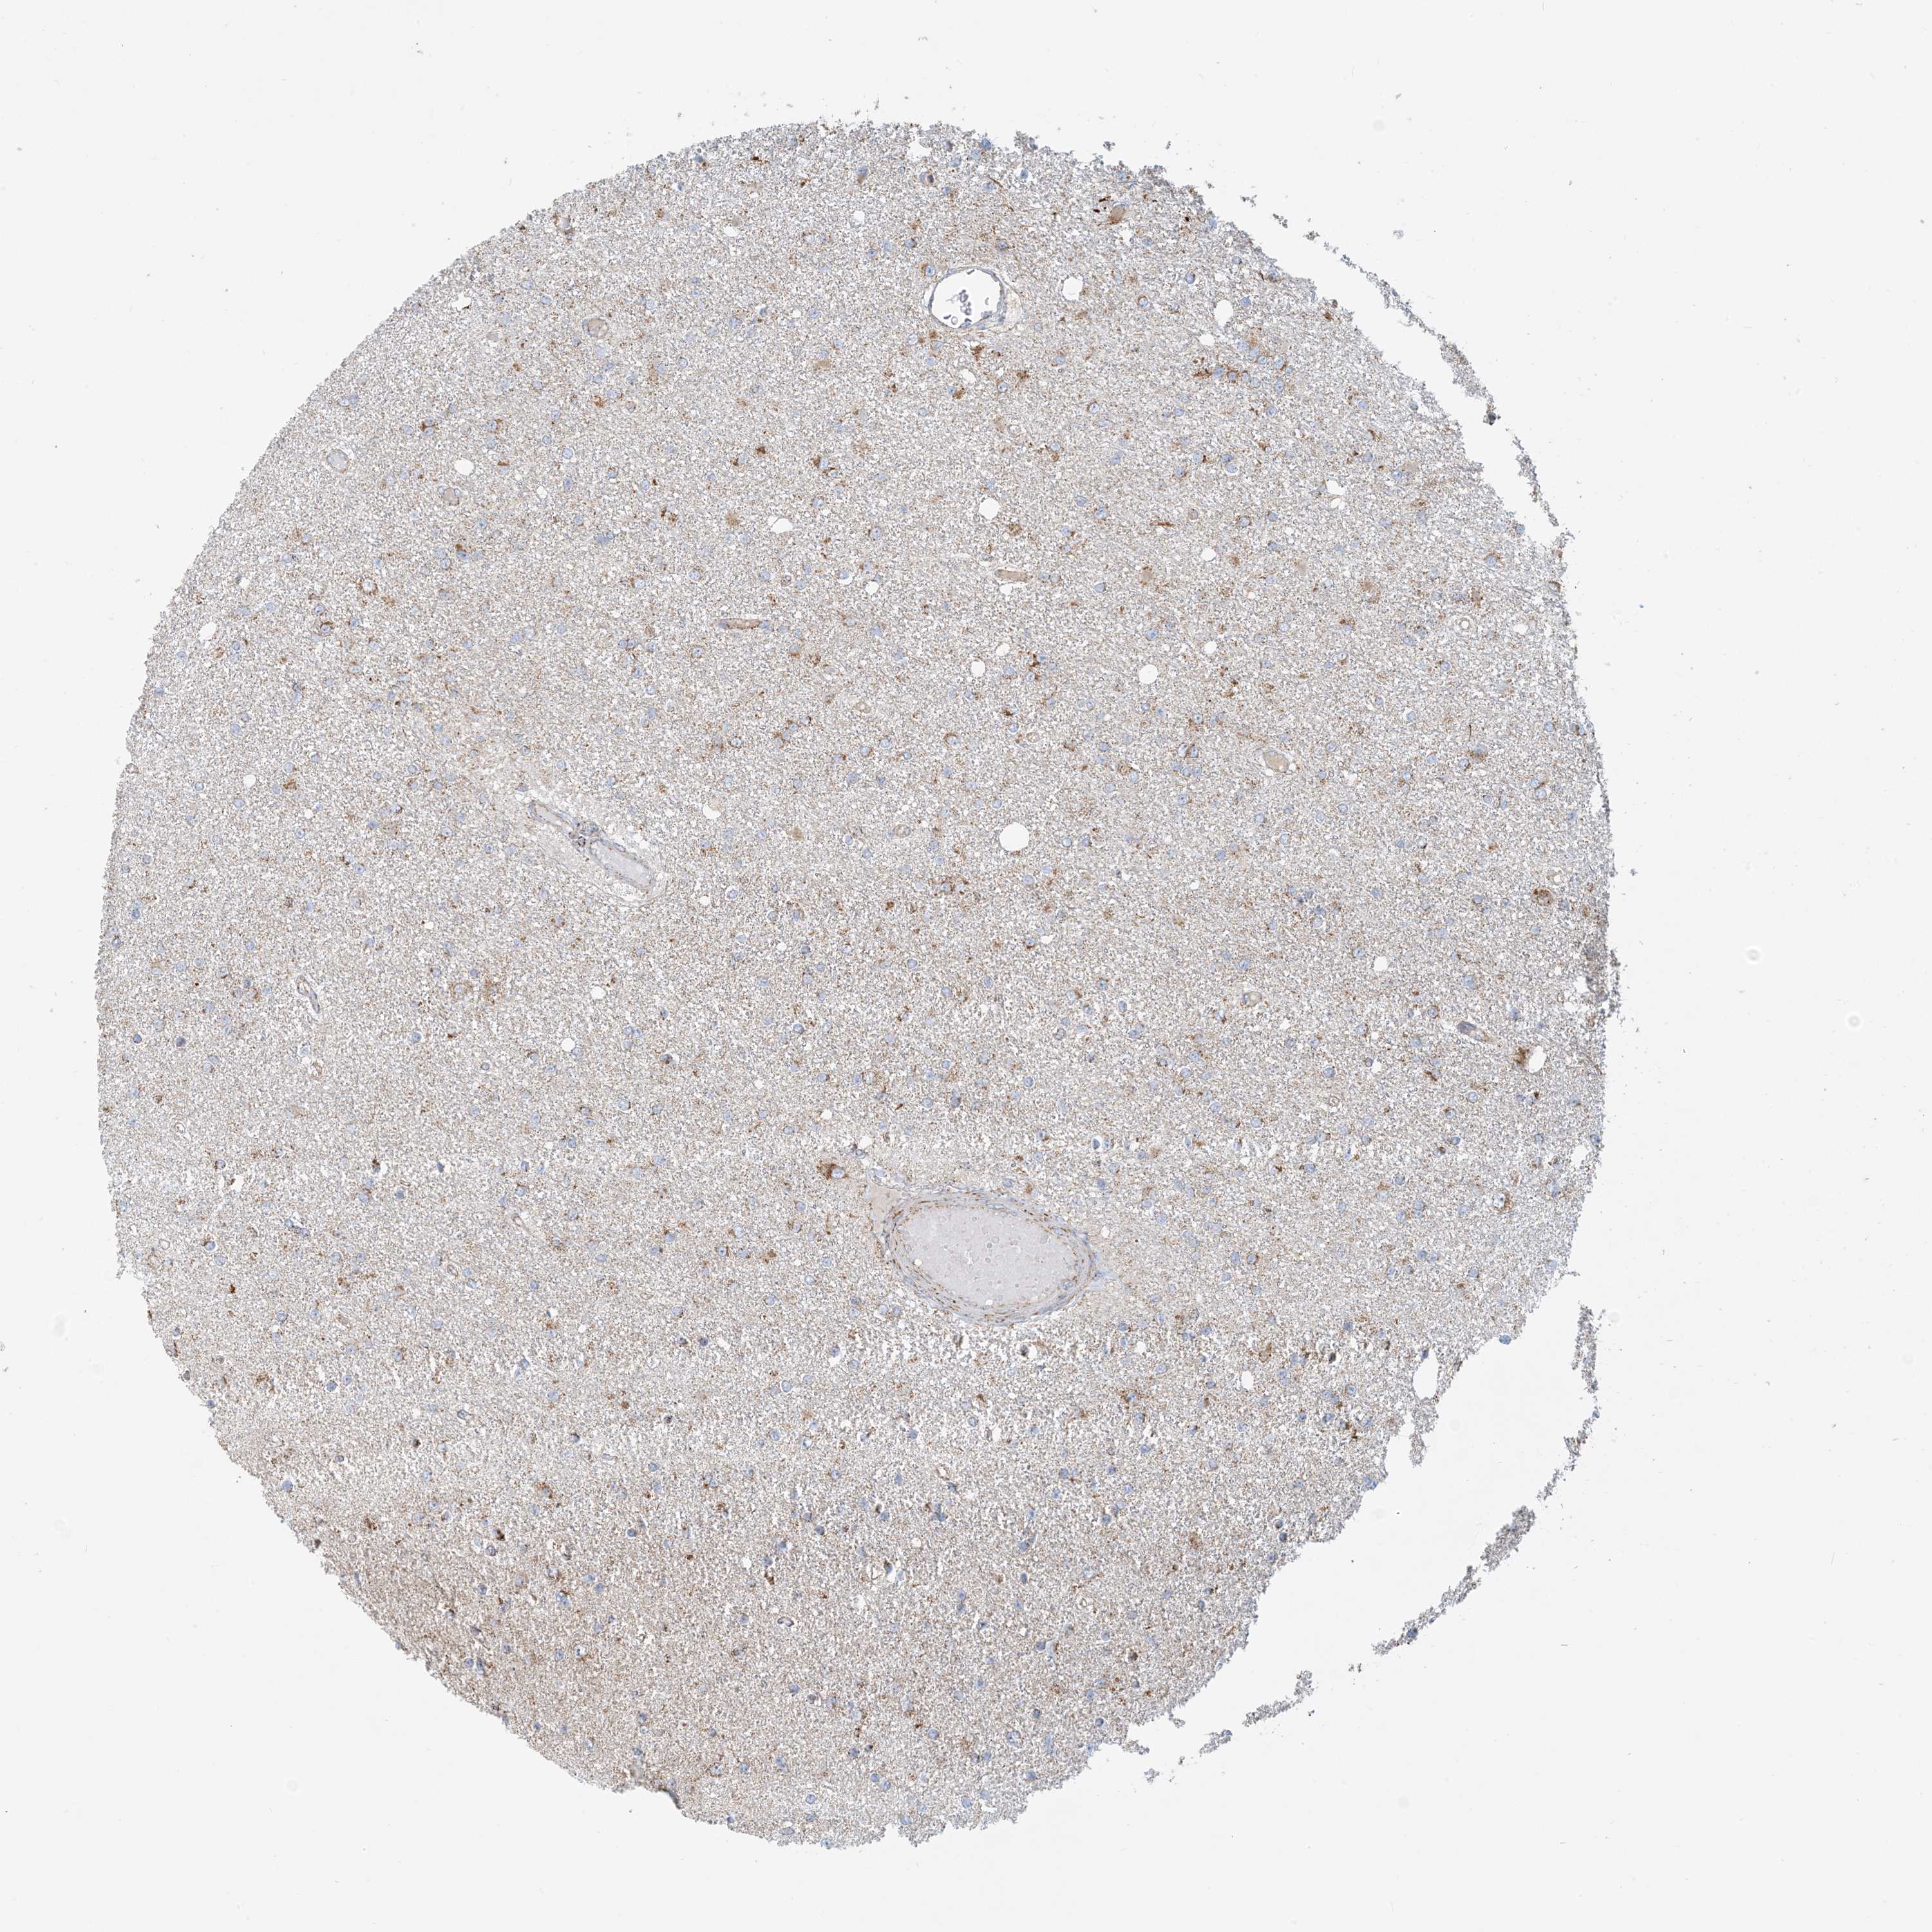

GLIOMA - Protein expressioni

A mouse-over function shows sample information and annotation data. Click on an image to view it in a full screen mode. Samples can be filtered based on level of antibody staining by selecting one or several of the following categories: high, medium, low and not detected. The assay and annotation is described here.

Note that samples used for immunohistochemistry by the Human Protein Atlas do not correspond to samples in the TCGA dataset.

Antibody stainingi

Antibody staining in the annotated cell types in the current human tissue is reported as not detected, low, medium, or high, based on conventional immunohistochemistry profiling in selected tissues. This score is based on the combination of the staining intensity and fraction of stained cells.

Each image is clickable and will lead to virtual microscopy that enables deeper exploration of all samples and also displays staining intensity scores, fraction scores and subcellular localization as well as patient and tissue information for each sample.

Antibody HPA031966

Staining

High

Medium

Low

Not detected

Intensity

Strong

Moderate

Weak

Negative

Quantity

>75%

75%-25%

<25%

None

Location

Nuclear

Cytoplasmic/membranous

Cytoplasmic/membranous,nuclear

Glioma, malignant, High grade

Glioma, malignant, Low grade

Glioblastoma, NOS